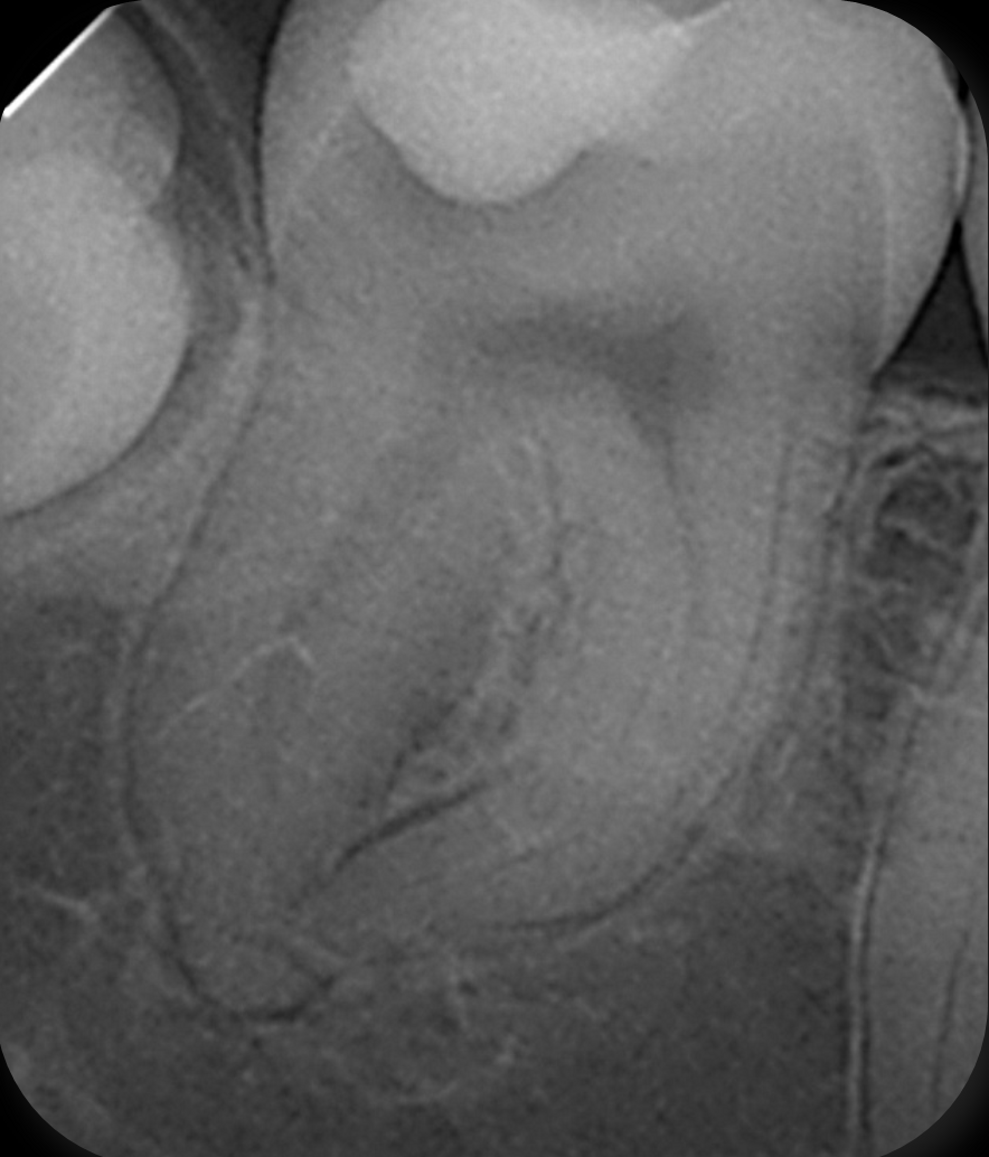

Fig. 5: Angulated post-op radiograph of the mandibular right second molar demonstrating the curvature of the mesial canals and the dense 3D obturation achieved up to working length.

For obturation, a modified warm vertical compaction technique was applied at 150 °C using a customised gutta-percha cone. For the final seal and in support of the healing process, ROEKO GuttaFlow bioseal (COLTENE) was chosen. The angulated postoperative radiograph revealed dense filling of all canals and of an additional lateral canal in the distal root, confirming that the modified warm compaction technique and GuttaFlow bioseal had effectively sealed the entire canal system (Figs. 4 & 5).